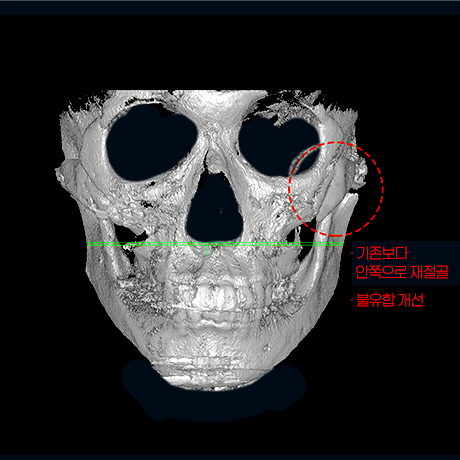

하이엘 절골 진행하여

45° 광대 축소

좌우 비대칭 개선

옆 광대 불유합 개선